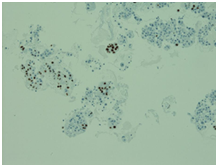

Initially, we thought about anaplastic thyroid cancer or lymphoma because of very rapid growth of thyroid mass. Thyroid ultrasound examination showed an enlarged thyroid gland; its structure was hypoechogenous and non-homogenous. Enlarged regional lymph nodes were also noted with obliteration of their ovoid morphology and loss of the echogenic hilum (Figure 1). Further imaging evaluation with contrast-enhanced computed tomography of the neck revealed an irregular tumor mass, which infiltrated neck soft tissue and vessels, causing airway stenosis up to 1 cm in diameter. The image was similar to hypo pharyngeal cancer. Also, by reason of voice changes, he was reviewed by an otolaryngologist and diagnosed a paralysis of one side vocal cord. Biochemical testing of thyroid function showed subclinical hyperthyroidism. After 1 week, thyroid ultrasound was repeated: thyroid was dramatically increased in size with its hypoechogenous and non-homogenous structure. On both lobes it was observed some up to 18 mm hyperechogenous and isoechogenous mixed nodes with pathological regional lymph nodes (Figure 2). Thyroid ultra sonography-guided fine-needle aspiration cytology (US-FNAC), cervical lymph nodes and laryngeal biopsies and particularly immunocytochemistry documented metastasis from primary lung cancer. Immunohistochemistry demonstrated that these cells were positive for TTF-1 and negative for thyroglobulin, consistent with metastatic disease from lung origin (Figure 3). The patient was deemed a nonsurgical candidate.

Figure 2 Immunohistochemistry demonstrating a malignant neoplasm of various-sized cells glandular in structure.

Figure 3 On immunocytochemistry, the malignant cells were focally positive to thyroid-transcription factor-1 (TTF-1).